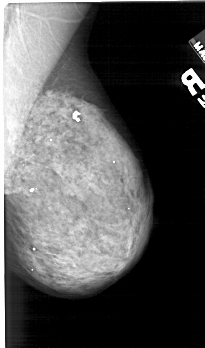

A_1420_1.LEFT_CC

LEFT_CC LINES 5176 PIXELS_PER_LINE 2791 BITS_PER_PIXEL 12 RESOLUTION 43.5 OVERLAY

FILE: A_1420_1.LEFT_CC.OVERLAY

TOTAL_ABNORMALITIES 1

ABNORMALITY 1

LESION_TYPE CALCIFICATION TYPE AMORPHOUS DISTRIBUTION CLUSTERED

ASSESSMENT 4

SUBTLETY 2

PATHOLOGY BENIGN

TOTAL_OUTLINES 1

BOUNDARY